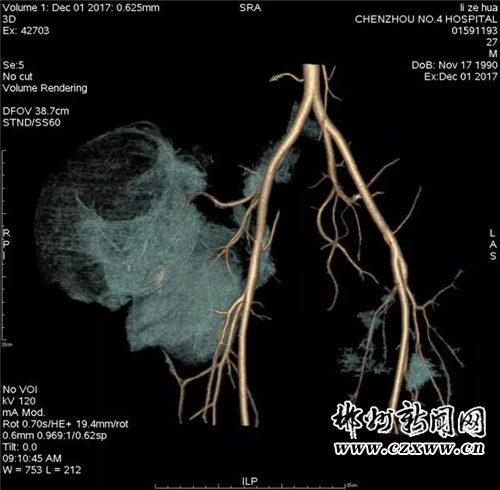

近日,患者感觉肿块突然增大并伴疼痛,觉得不能再耽搁了,遂抱以试试看的心态来我院就诊。入住普外科后,科主任李洪春主任医师亲自接诊并仔细为患者检查,患者右侧臀部外侧见约12*14*10cm大小肿物,不规则型,质软,压痛,活动欠佳,边界清,皮肤无溃烂。穿刺可抽出血性液体。立即予以完善臀部CT。

为进一步明确诊断与治疗,科室立即申请医院副院长放射科主任郑海军主任医师会诊探讨,经讨论认为:患者血管瘤营养支可能来自右侧髂内动脉分支臀上、下动脉,血运丰富,血流量大,一旦再次出血,后果将不堪想象,应尽快安排手术取出该“定时炸弹”。可问题是,该肿块血运如此丰富,术中出血不可估量,该如何避免呢?此时,李洪春主任立即联系介入科主任薛小刚副主任医师会诊,会诊后立即行血管介入栓塞术,以先切断肿块的血运,防止术中大出血。行血管介入栓塞术后,再在做好其他术前准备和积极备血的前提下,普外科予患者行右侧臀部巨大假性动脉瘤切除术。